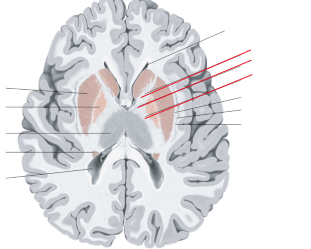

nucleus caudatus

putamen

globus pallidus

capsula interna (corona radiata)

capsula externa

capsula extrema

fornix

laterale ventrikels (I en II)